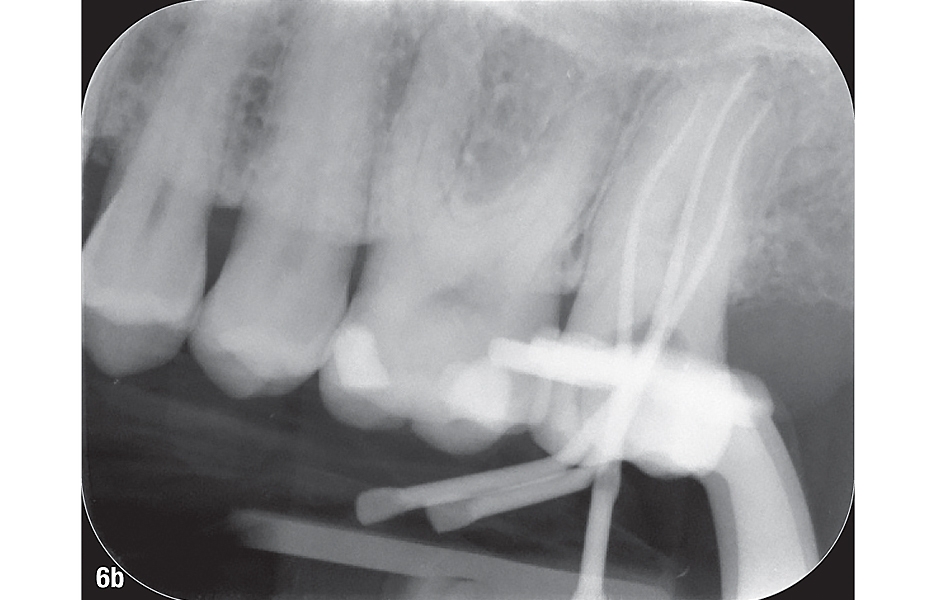

Sekvence elektrochemické irigace probíhala podle stejného protokolu jako při prvním ošetření. Po poslední irigační sekvenci byly kanálky dobře vysušeny pomocí obzvláště úzké endodontické sací kanyly, což snížilo potřebné množství papírových čepů. Papírové čepy je dobré kontrolovat, zda již jsou suché a zda tedy v kanálku nezůstala tekutina. Jako centrální byl zvolen gutaperčový čep HyFlex EDM 30/.04, který odpovídá systému požitých nástrojů (obr. 6a–c).

Centrální čepy HyFlex EDM stejné délky byly použity pro termoplastickou 3D obturaci tří kořenových kanálků tekutou gutaperčou. Biokeramický sealer AH Plus (Dentsply Sirona) poskytl požadované utěsnění. V tomto případě bylo naprosto dostatečné potáhnout sealerem pouze spodní část gutaperčových čepů. Dále byly vstupy do kanálků zakryty tekutým kompozitem v odstínu A1 v kombinaci s odpovídajícím leptacím gelem, primerem a adhezivem. Pro finální rekonstrukci byl použit vysoce kvalitní kompozit BRILLIANT EverGlow Flow (COLTENE) – opakní v odstínu A3. Konečný rentgenový snímek potvrdil spolehlivé utěsnění tří kanálků v zubu 27 (obr. 7).

Obr. 6a–c: Zavedení centrálních gutaperčových čepů HyFlex EDM 30/.04. a) intraorální pohled, b) rentgenový snímek, c) jednotlivé gutaperčové čepy.

6b: Rentgenový snímek.